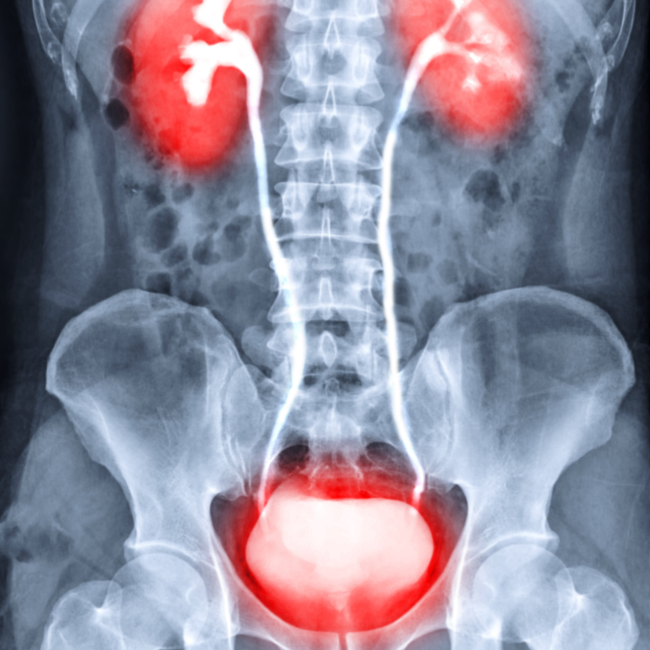

과민성 방광 증후군의 증상

빈뇨 : 하루 8회 이상 소변을 본다

야간뇨 : 수면 중 소변을 2회 이상 본다

절박성 요실금 : 강하고 갑작스럽게 소변을 보고 싶은 느낌이 있으면서 참지 못하고 소변을 지리는 증상